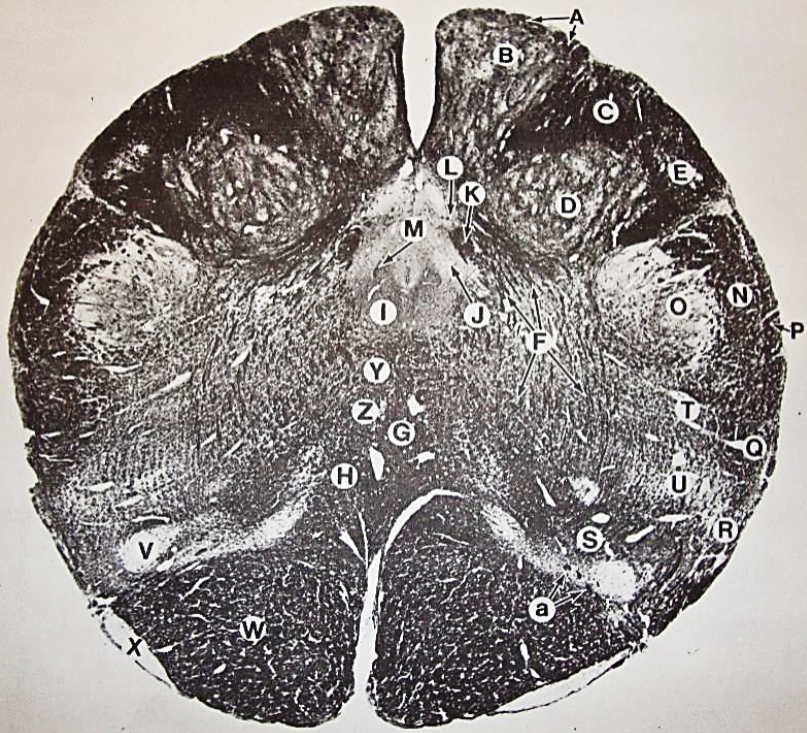

A

Fasciculus gracilis

B

gracile nucleus

C

fasciculus cuneatus

D

cuneate nucleus

E

spinal trigeminal tract

F+G collectively

spinal trigeminal nucleus

H

accessory nucleus

I

pyramidal decussation

J

rubrospinal tract

K

posterior spinocerebellar tract

L

anterior spinocerebellar tract

M

lateral spinothalamic tract

N

anterior spinothalamic tract

O

lateral vestibulospinal tract

P

medial longitudinal fasciculus

Q

tectospinal tract